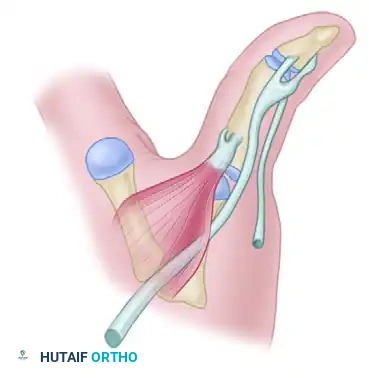

SURGICAL TECHNIQUE: THUMB METACARPOPHALANGEAL ARTHROPLASTY

The following step-by-step technique details the approach for a thumb MCP arthroplasty, addressing the specific anatomical nuances of the extensor pollicis longus (EPL) and extensor pollicis brevis (EPB).

1. Positioning and Exposure

- Anesthesia: Regional block (supraclavicular or axillary) or general anesthesia.

- Positioning: Supine with the operative arm extended on a radiolucent hand table. A well-padded pneumatic tourniquet is applied to the upper arm and inflated to 250 mm Hg after exsanguination.

- Incision: Expose the metacarpophalangeal joint through a longitudinal dorsal oblique or gently curved incision centered over the joint. This approach avoids scar contracture directly over the flexion crease and provides excellent access to the extensor mechanism.

2. Extensor Mechanism Release

- Carefully dissect the subcutaneous tissues, preserving the dorsal sensory branches of the radial nerve.

- Identify the extensor apparatus. Release the extensor pollicis longus (EPL) from the extensor expansions on each side.

- Identify and release the extensor pollicis brevis (EPB) from its insertion at the base of the proximal phalanx. Tag the EPB with a non-absorbable suture for later reattachment.

3. Joint Preparation and Bone Resection

- Perform a dorsal capsulotomy to expose the articular surfaces.

- Metacarpal Resection: Resect the metacarpal head perpendicular to the long axis of the metacarpal shaft. It is critical to leave the metaphyseal flare of the metacarpal intact to provide a broad, stable base for the implant hinge.

- Ligament Preservation: Meticulously preserve the collateral ligaments. Unlike some aggressive resections in the past, modern techniques emphasize retaining these structures to ensure postoperative coronal plane stability.

- Proximal Phalanx Preparation: Leave the base of the proximal phalanx intact whenever possible. However, if additional space is required to accommodate the hinge of the prosthesis without buckling, remove a minimal portion of the articular cartilage and subchondral bone using an oscillating saw or rongeur.

4. Canal Preparation and Trialing

- Utilize specialized broaches and reamers to prepare the medullary canals of both the metacarpal and the proximal phalanx.

- Insert temporary trial prostheses to determine the optimal size. The goal is to select the largest size that the metacarpal shaft will comfortably accept without causing cortical fracturing. The implant stems should fit snugly, and the central hinge should sit flush against the resected bone surfaces.

5. Preparation for Soft Tissue Reconstruction

- Before inserting the final implant, prepare the proximal phalanx for the reattachment of the EPB.

- Drill small osseous holes in the dorsal base of the proximal phalanx.

- Pass a robust, non-absorbable suture (e.g., 2-0 FiberWire or Ethibond) through these holes so that it is pre-positioned for the reattachment of the EPB after the prosthesis has been seated.

6. Implant Insertion

- Thoroughly irrigate the medullary canals to remove bone debris and marrow fat.

- Insert the final silicone implant using a "no-touch" technique with smooth forceps to avoid scratching the elastomer, which can create stress risers and lead to premature failure.

- Optional: If needed due to irregular, sharp, or cystic bony surfaces, insert metal sleeve "grommets" into the canals prior to the silicone implant. These titanium shields protect the silicone hinge from abrasive shear forces.

7. Soft Tissue Reconstruction and Closure

- EPB Reattachment: Reattach the extensor pollicis brevis to the pre-drilled holes in the proximal phalanx. Ensure this is done under sufficient tension to allow robust proximal phalangeal extension.

- Extensor Expansion Repair: Repair the extensor expansion meticulously over the insertion of the EPB tendon.

- EPL Advancement: Advance and repair the extensor pollicis longus tendon, ensuring it is perfectly centered over the extensor expansion to prevent postoperative subluxation.

- Distal Joint Management: Assess the interphalangeal (IP) joint. If severe hyperextension or instability is present (common in Type I deformities), pin the distal joint with a smooth Kirschner wire, or perform a concurrent IP joint arthrodesis.